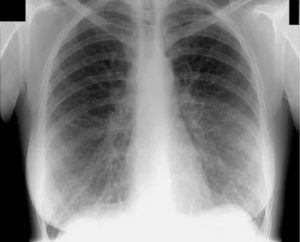

На снимках по-разному отображаются различные внутренние органы. Например, бронхи и сердце появляются в виде световых пятен. Легочные ткани здорового органа на рентгеновском изображении будут смотреться однородными и равномерными.

Если имеются патологические изменения в легких, то на картинке изображения будут видны как более темные участки или более светлые, по сравнению с оригиналом. Более темные пятна свидетельствуют о наличии воспаления и увеличении плотности ткани легкого в этом месте. Более светлые пятна обозначают “рыхлость”, понижение плотности ткани на данном участке.

Простой острый бронхит увидеть на рентгеновском снимке невозможно, визуализации поддаются только обструктивные и хронические длительно текущие формы заболевания. Рассмотрим примеры того, как выглядит бронхит на рентгеновских снимках:

На фото 1 и 2 видно, как выглядит бронхит на рентгеновских снимках, а точнее, признаками заболевания являются:

- изменение размера и структуры корней легких,

- нечеткость его контуров,

- изменение легочного рисунка (как правило, усиление),

- утолщение стенок бронхов при хроническом бронхите (симптом «трамвайные рельсы» фото 3).